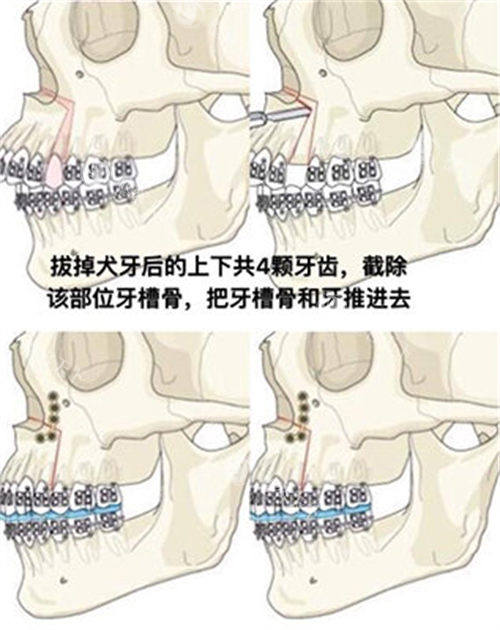

术中流程划线设计→消毒麻醉→小创口入路→骨骼重塑→止血缝合,全程心电监护。